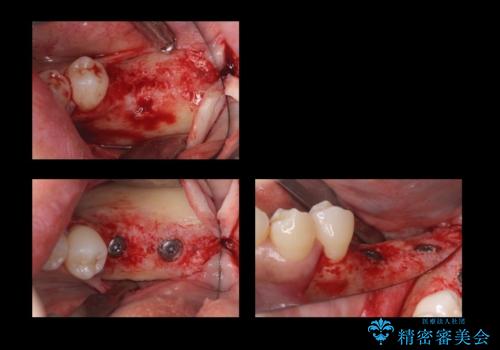

左右の第二大臼歯は虫歯がひどく抜歯が必要な状態でした。

また、左下の第一大臼歯は歯が内側から吸収してしまう状態(外部吸収)が生じており、患者様と相談の上抜歯しました。

合計3本の奥歯を抜歯したところに、インプラント治療を行っています。

外科手術時には麻酔医により静脈内鎮静法を行っています。

静脈内鎮静法は、手術時の記憶がなくなり、うたた寝をしたような状態で手術を終えられるため、恐怖を味わうことなく手術を受けることが可能です。